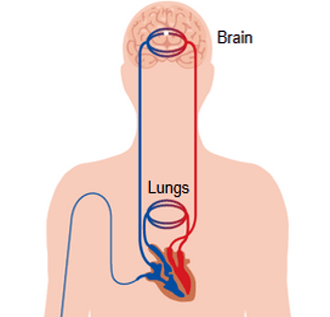

After its injection, the contrast agent travels from the vein through the pulmonary and systemic circulations to the vessels of the brain.

As the iodine-based contrast agents cannot cross the blood-brain barrier, the bolus exits most parts of the brain immediately after its arrival. This can be seen in cine-mode as a pattern of increasing and decreasing x-ray attenuation of each voxel, marking the arrival and departure of the contrast agent.